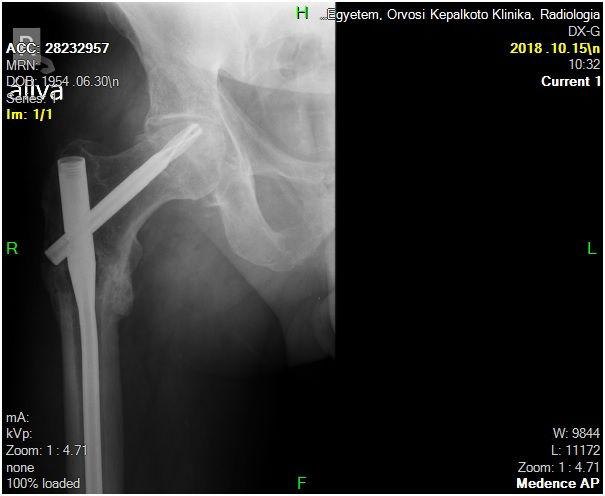

29 éves pályám során közel ezer térdprotézist és több mint kétezer csípőprotézist ültettem be. Az utóbbi években egyre több, nagy műszer igényű, összetett protézis revíziós műtétet végzek.

Fő érdeklődési köröm a biomechanika, műszerfejlesztés, új műtéti technikák kidolgozása és a nagyízületi endoprotetika.